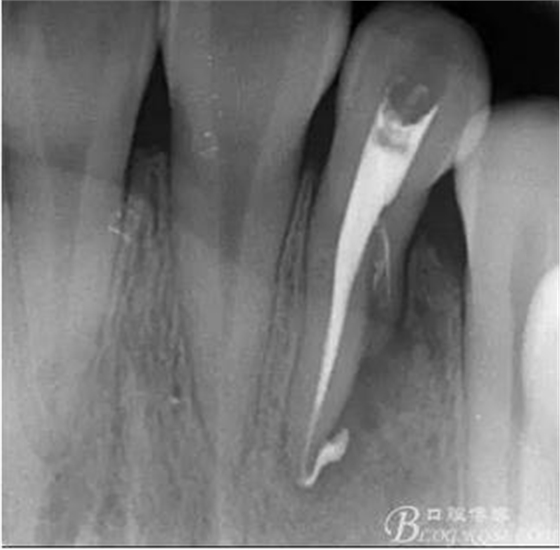

(6)復(fù)診:原暫封材料再位,牙周無明顯異常與不適,常規(guī)清潔根管,H銼清除根管內(nèi)維他,次氯酸鈉終末消毒,干燥根管,單尖測壓發(fā)充填根管,術(shù)后拍片到位。